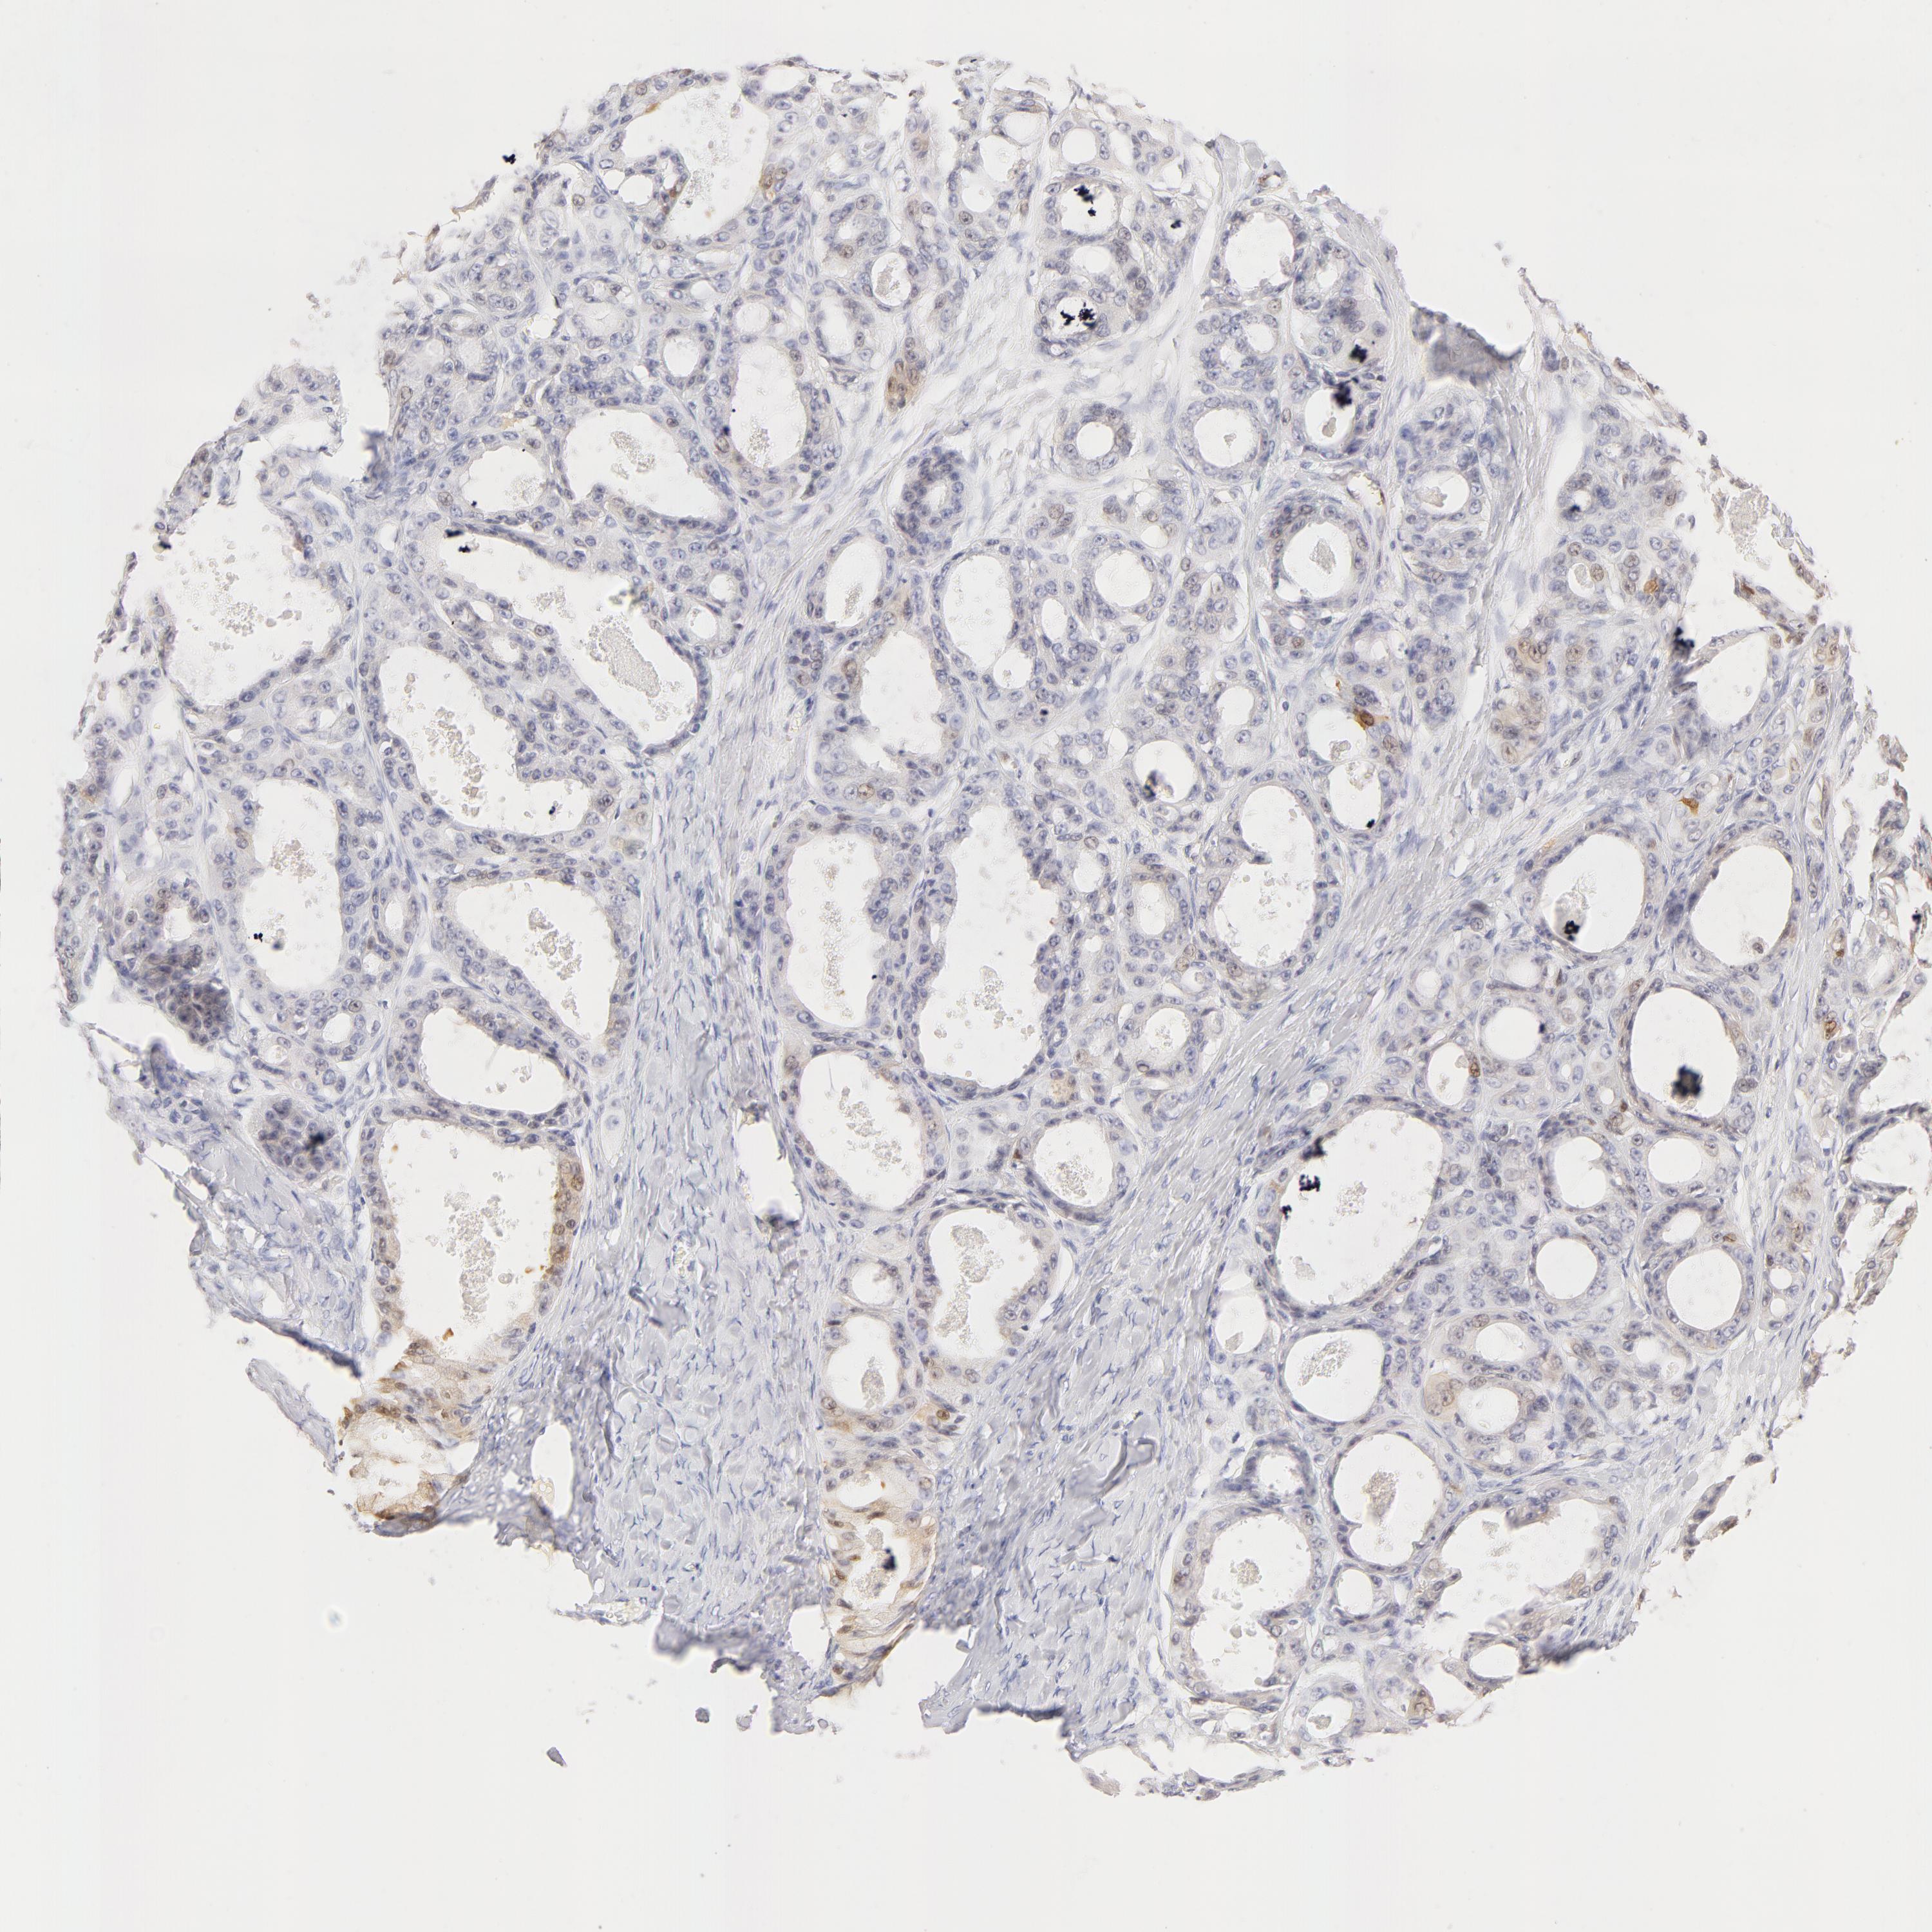

OVARIAN CANCER - Protein expressioni

A mouse-over function shows sample information and annotation data. Click on an image to view it in a full screen mode. Samples can be filtered based on level of antibody staining by selecting one or several of the following categories: high, medium, low and not detected. The assay and annotation is described here.

Note that samples used for immunohistochemistry by the Human Protein Atlas do not correspond to samples in the TCGA dataset.

Antibody stainingi

Antibody staining in the annotated cell types in the current human tissue is reported as not detected, low, medium, or high, based on conventional immunohistochemistry profiling in selected tissues. This score is based on the combination of the staining intensity and fraction of stained cells.

Each image is clickable and will lead to virtual microscopy that enables deeper exploration of all samples and also displays staining intensity scores, fraction scores and subcellular localization as well as patient and tissue information for each sample.

Antibody HPA001550

Antibody CAB010102

Carcinoma, endometroid

Cystadenocarcinoma, serous, NOS

Cystadenocarcinoma, mucinous, NOS

Carcinoma, NOS